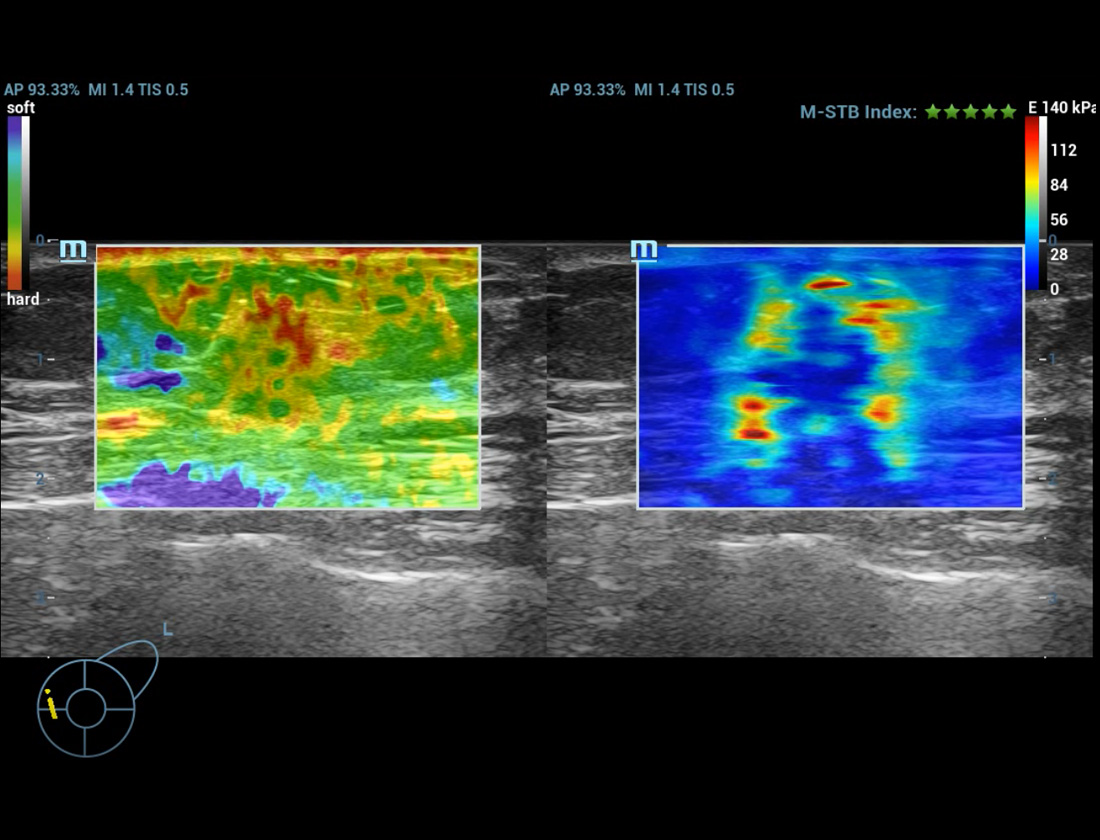

Strumenti di analisi multiparametrica M-Reference

M-Ref. C&E

M-Ref. C&E tumore maligno al seno

M-Ref. C&E supporta la visualizzazione del contrasto e della STE in un unico piano per una valutazione comparativa della perfusione e dell'elasticitĂ .

M-Ref. E Compare

M-Ref. E Compare tumore maligno al seno

M-Ref. E Compare supporta la visualizzazione dell'elastografia strain in tempo reale e della STE in un unico piano per la valutazione della rigiditĂ dei tessuti.